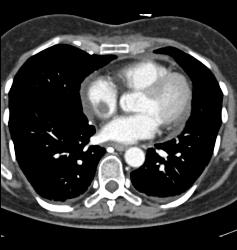

SVC Occlusion With Collaterals. SVC Occlusion Was Due to Tumor